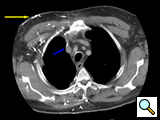

Diagnosis starts with a physical exam with a particular emphasis on the head and neck area. Chest x-ray may show a hilar mass in the case of an obstructing bronchogenic carcinoma or mediastinal mass (e.g. lymphoma) or mediastinal calcification (e.g. histoplasmosis). Infused computed tomography of the head and neck and chest with a venous phase will show characteristic pictures of numerous superficially draining contrast-filled venous collaterals (Figure 1). It will allow assessment of the mediastinum and help exclude compressive masses in the case of an externally compressive hilar or anterior mass, or exclude extensive intravascular clot secondary to a pacemaker electrode. It will also help determine the patency of the jugular and subclavian veins.

Figure 1: Infused CT scan demonstrating extensive contrast filled superficial venous collaterals (yellow arrow) overlying the right hemithorax and a small contrast-filled "trickle" draining centrally into a clot-filled superior vena cava (blue arrow).